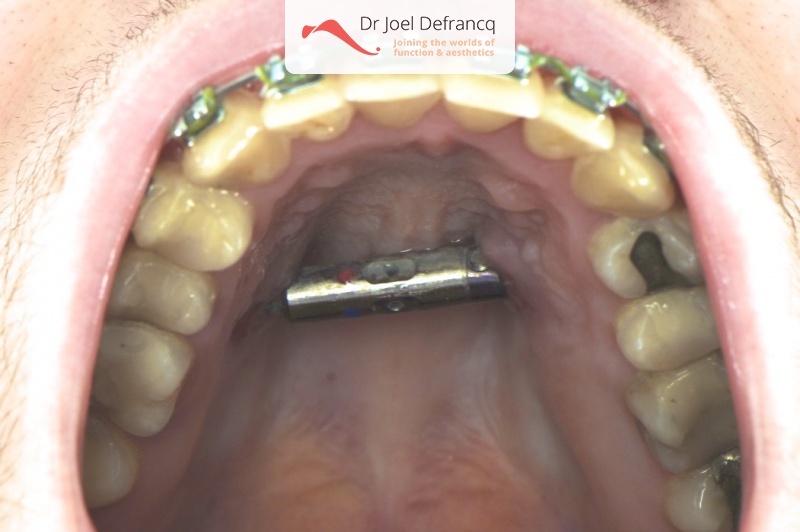

- Verbreden bovenkaak (Smile distractor)